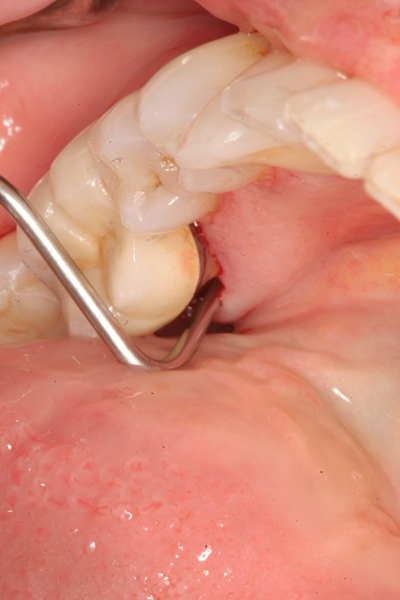

牙齦炎

牙齦炎圖片

牙齦炎和牙周炎